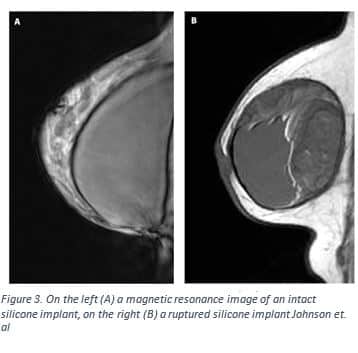

Both saline and silicone breast implants have a silicone shell16. They differ in the filler material, consistency, and how they are placed within the capsule. Saline breast implants are filled with sterile salt water whereas silicone implants are filled with a silicone gel17. Implant rupture is easier to detect with a saline implant versus silicone, because the free silicone generally remains in the capsule around the implant whereas the saline implant will deflate and the salt water within will be absorbed by the body17,18. Silicone gel implants have a more natural look and consistency than saline implants, but their placement is slightly more invasive17. A saline implant is inserted while it is collapsed, and is then filled when it is within the capsule17. Mentor is the only company that in 2015 had a saline implant that could be further adjusted after the operation 2. A silicone implant requires a larger incision to be placed and the size cannot be adjusted17. Both saline and silicone implants have similar risk factors: capsular contracture, pain, infection, changes in breast or nipple sensation, and implant rupture17,18.